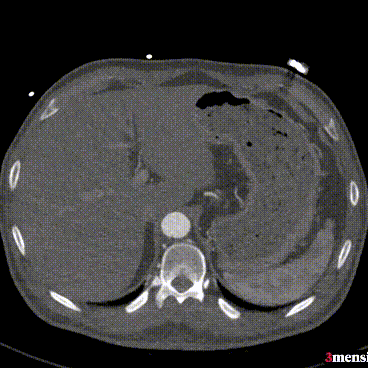

案例二(短瘤颈+梯形瘤颈):患者近端瘤颈长度不足1cm,且伴有大量附壁血栓。选用适当oversize的支架,结合Reverse技术释放,支架主体自动“寻找”并适应最佳的贴附区域,最终造影显示无明确内漏。